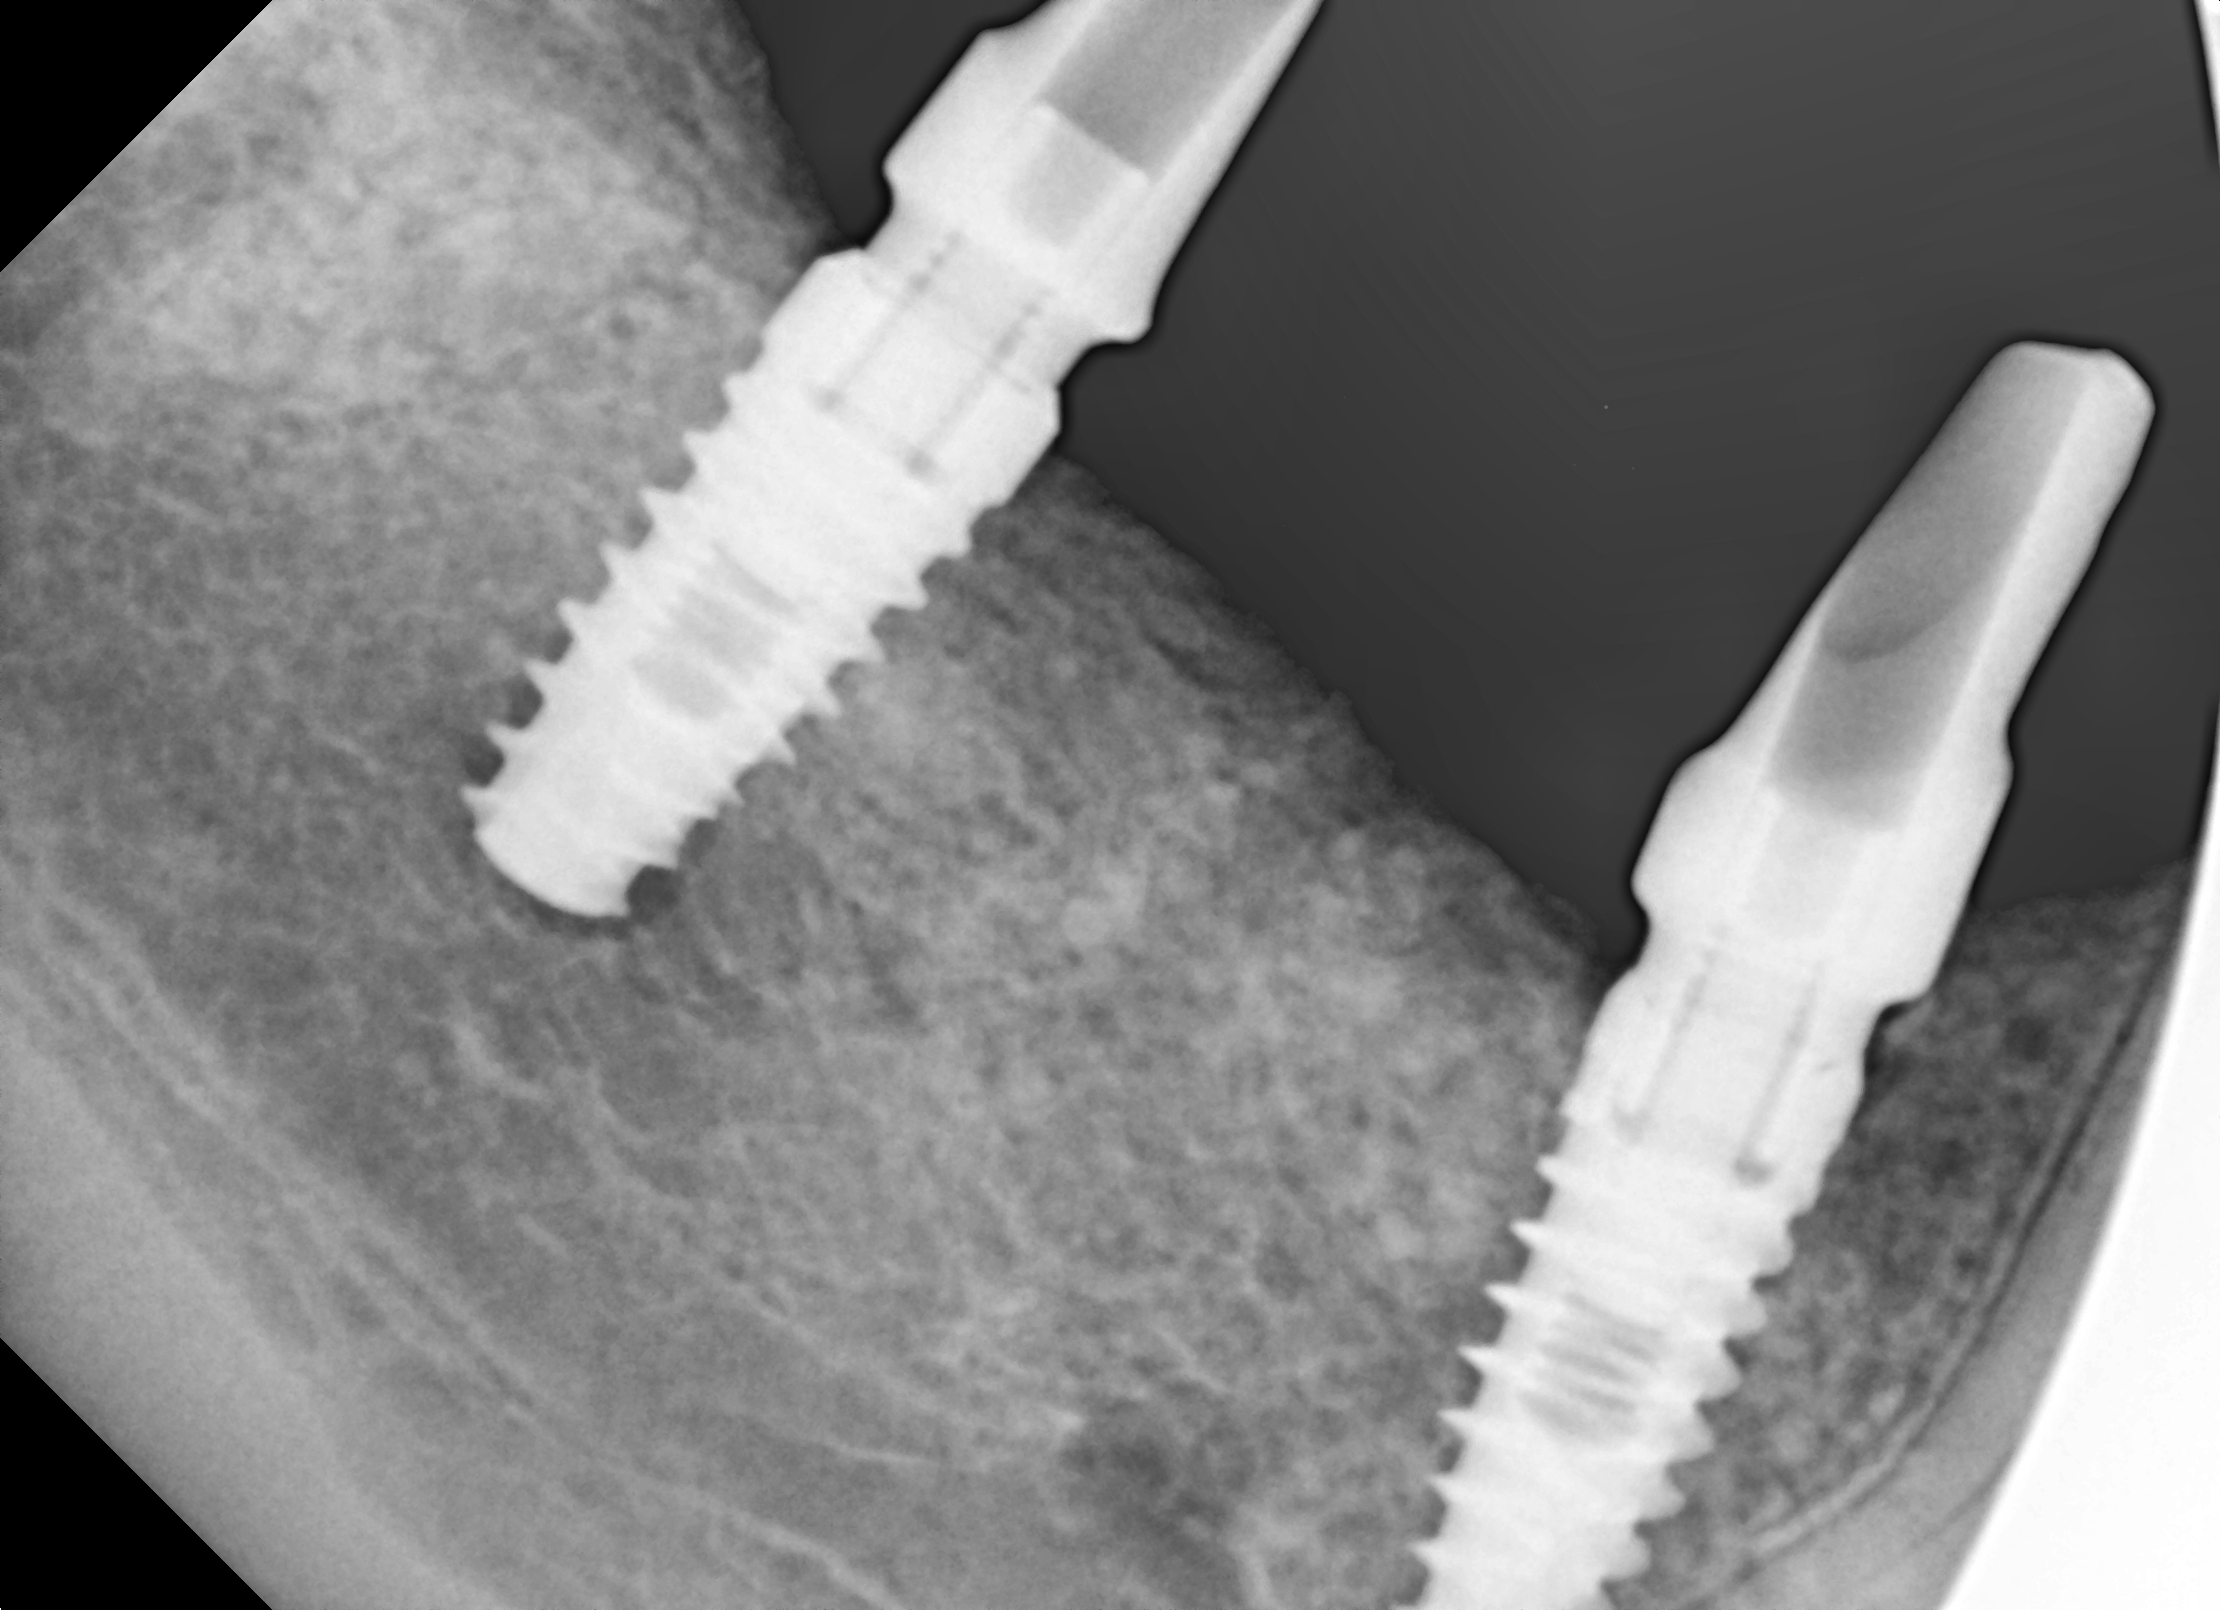

Regenerację blaszki przedsionkowej potwierdzono także klinicznie po odwarstwieniu płata podczas zabiegu planowej implantacji. Zmierzono szerokość wyrostka na poziomie 7-8 mm (ryc.14). Po wyrównaniu płaszczyzny wyrostka (ryc. 15) wykonano łoża dla implantów śrubowych w okolicy 45 (dł. 10 mm, śr. 3.7 mm) i 46/47 (dł. 10 mm, śr. 4.1 mm) (ryc.16), które wprowadzono w kość z momentem obrotowym około 25 Ncm. Ranę zaopatrzono szwami (PTFE – politetrafluoroetylen 4-0, igła odwrotnie tnąca, profil 3/8 koła długość 16 mm) (ryc.17).

Ryc. 16. Wprowadzenie implantów w okolicy 45(3.7,10 mm) i 46-47( 4.1,10 mm). Ryc. 17. Zaopatrzenie rany.

Ryc. 18. Kontrola położenia mplantu w pozycji 45.

Ryc. 19. Kontrola położenia implantu w pozycji 46-47.